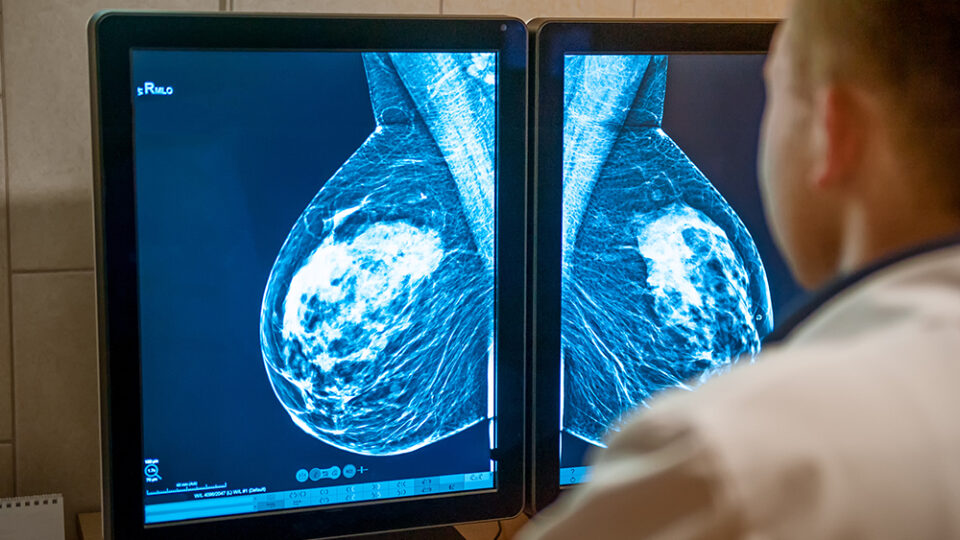

Neue Schwachstelle bei therapieresistentem Brustkrebs entdeckt

Forschende der Philipps-Universität Marburg haben einen neuen Ansatz zur Behandlung des hormonrezeptor-positiven, HER2-negativen Mamakarzinoms identifiziert. In experimentellen Modellen konnten sie zeigen, dass Tumorzellen, die gegen moderne Standardmedikationen wie CDK4/6-Inhibitoren resistent geworden sind, eine bislang unerkannte metabolische Verwundbarkeit entwickeln.